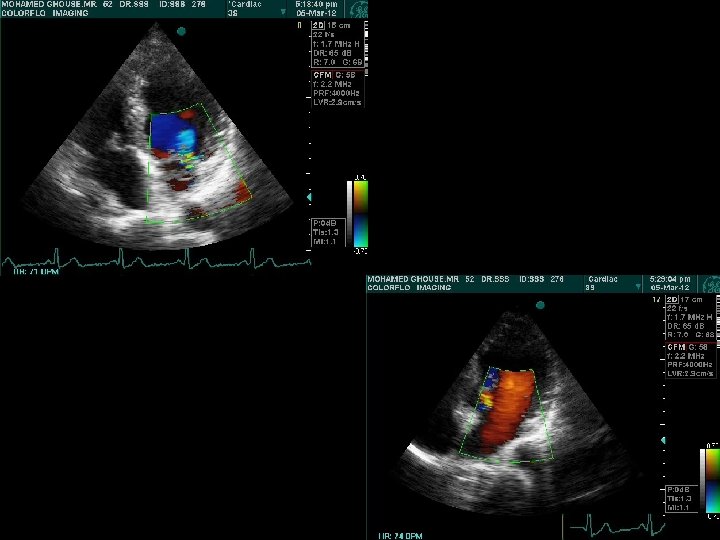

Dynamic Auscultation • Source of murmur : Right Heart ~ Left Heart • Differentiate closely simulating murmurs Outflow ~ Regurgitatnt murmur • Differentiate flow murmurs from those of structural deformity : Austin Flint ~ MS • Differentiate Dynamic from Fixed Obstructions

Respiration • Left sided events are better heard in expiration MR, MS, AS & AR murmurs LV S 3 & S 4, Mitral OS Click & murmur of MVP occur later @ PV – LA gradient increases > ↑ LV filling @ Lung overlap decreases @ Apnea for faint AR murmur